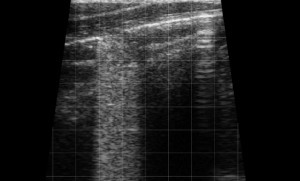

–Canine and Feline abdominal ultrasound videos were generously provided by the Cummings School of Veterinary Medicine at Tufts University.

–Equine distal limb ultrasound videos and bovine ultrasound videos were generously provided by the Virginia-Maryland College of Veterinary Medicine at Virginia Tech.